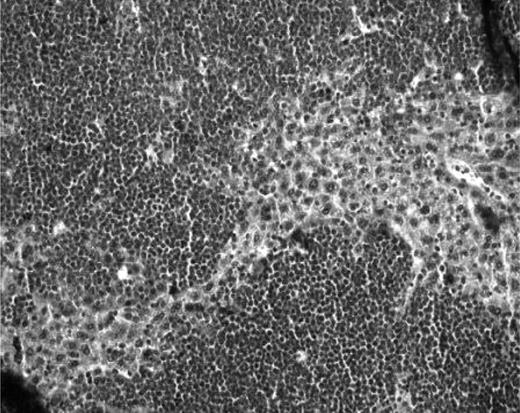

Macroscopic and histologic analysis of ovarian fragments recovered from the mice after 6 months' grafting. (A) Macroscopic view of normal frozen-thawed ovarian grafts. (B) Macroscopic view of an enlarged ovarian graft. Note the stitches at both ends. (C) Histologic aspect of a normal ovarian-xenografted fragment. Five ovarian follicles can be recognized in a cellular stroma surrounded by a fibrotic area. Original magnification ×100. (D) Human ovarian graft from a patient with ALL with massive cellular invasion. Note the 6-0 Prolene stitch in the graft (arrow). Original magnification ×50. (E) Human follicle encircled by a large number of lymphocytes. Normal ovarian stroma is no longer present. Original magnification ×100. (F) Massive lymphocytic invasion of the ovarian graft. The histologic abnormalities observed in these lymphocytes were identified as malignant in nature and attributed to leukemic invasion. Original magnification ×200.

In mice grafted with ovarian tissue from CML patients, serial sections of grafts did not show the presence of malignant cells, and human ovarian xenografts had a normal histologic appearance (Figure 2C).

For grafts issuing from ALL patients, 5 of 12 showed obvious invasion by lymphoblasts. Histology confirmed disease in 4 mice presenting with macroscopic signs of malignancy, plus case 18, which exhibited leukemic invasion at microscopic analysis (Figure 2D-F). Figure 2E shows one of these 5 xenografts (case 8), with massive proliferation of malignant lymphocytes, in the middle of which a secondary-stage follicle is clearly visible.